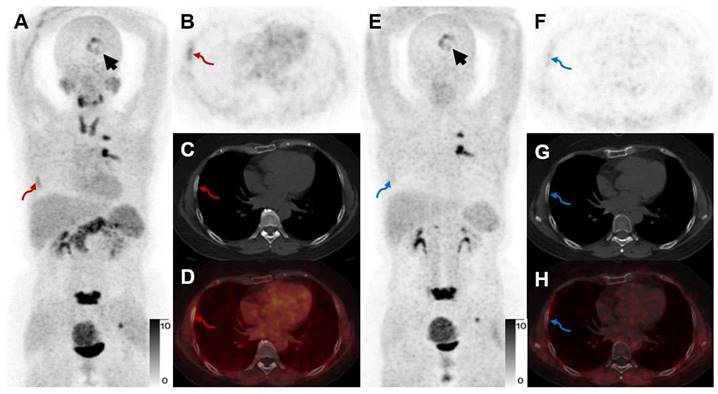

A 52-year-old woman with IAC (Participant No. 44) underwent two PET scans. [68Ga]Ga-FAPI-RGD showed higher uptake in brain metastasis than [68Ga]Ga-FAPI (SUVmax, 7.7 vs. 5.6, black arrows). One more rib lesion with high uptake was found (A-D, red arrows, SUVmax 4.5) by [68Ga]Ga-FAPI-RGD PET/CT while not detected by [68Ga]Ga-FAPI PET/CT (E-H, blue arrows), which had been confirmed as a metastatic lesion on previous whole-body bone scan.